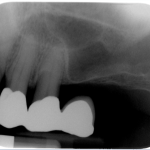

The bone used in a sinus lift may come from your own body (autogenous bone), from a cadaver (allogeneic bone) or from cow bone (xenograft). You will need X-rays taken before your sinus lift so the dentist can study the anatomy of your jaw and sinus. You also may need a special type of computed tomography (CBCT) scan. This scan will allow the dentist to accurately measure the height and width of your existing bone and to evaluate the health of your sinus.

The key to a successful and long-lasting dental implant is the quality and quantity of jaw bone to which the implant will be attached. If bone loss has occurred due to injury or periodontal disease, a sinus augmentation can raise the sinus floor and allow for new bone formation.